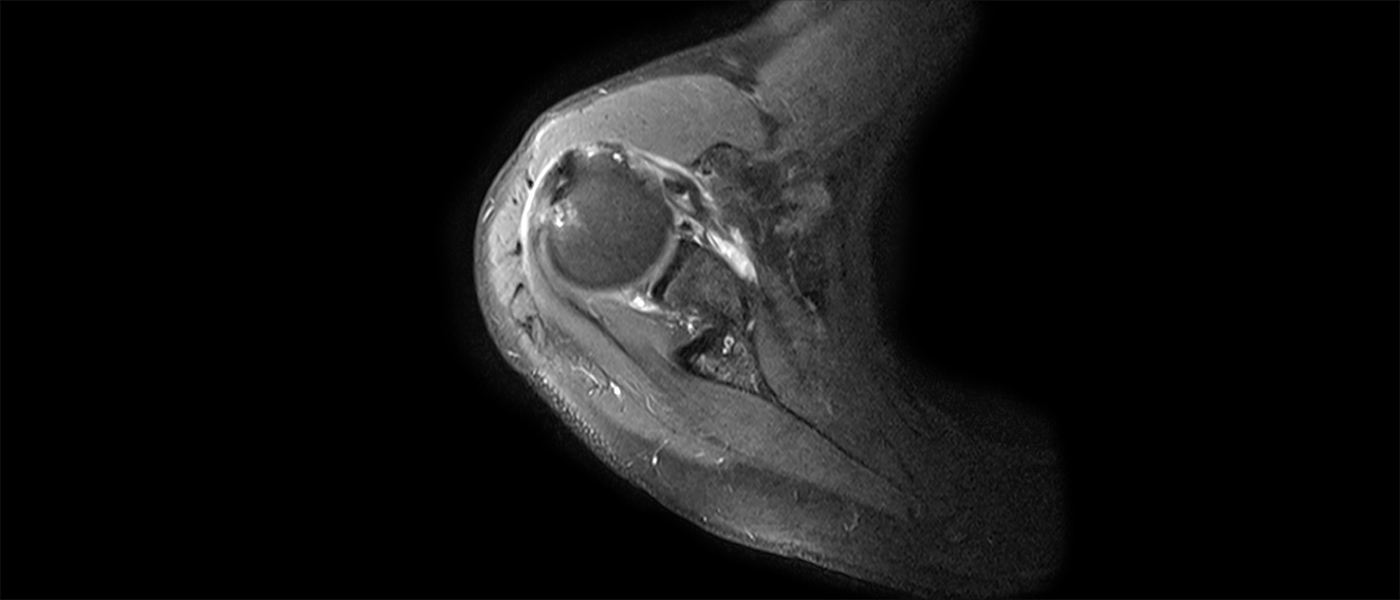

The goal of this course is to further develop the experienced surgeon’s understanding of soft-tissue injuries around the shoulder and enhance the surgical skills needed to treat this patient population. This course will help participants enhance their technical skills, identify optimal treatment decisions to improve postoperative function and patient satisfaction, and better manage complex and rare cases.

- Arthroscopic Management of Rotator Cuff Tears

- Arthroscopic Management of Glenohumeral Instability

Upon completion of this event, participants will be able to Identify shoulder anatomy and pathology related to sports and soft-tissue injuries Obtain an injury-specific history and perform a detailed physical exam of the shoulder Interpret appropriate radiographic images Create an accurate diagnosis Describe the treatment options and select an appropriate plan Perform arthroscopic and/or open procedures based on best scientific guidelines Develop an appropriate postoperative rehabilitation plan Identify and manage potential intra- and postoperative complications Review common, difficult, failed, and revision cases and explain how to manage poor outcomes -